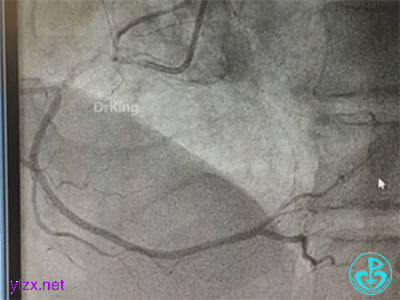

冠脉造影

右冠脉近中段不规则狭窄。短左主干中度狭窄,前降支开口严重狭窄,多功能造影导管推注造影剂时无反流,导管退出左主干开口造影发现左主干狭窄严重。